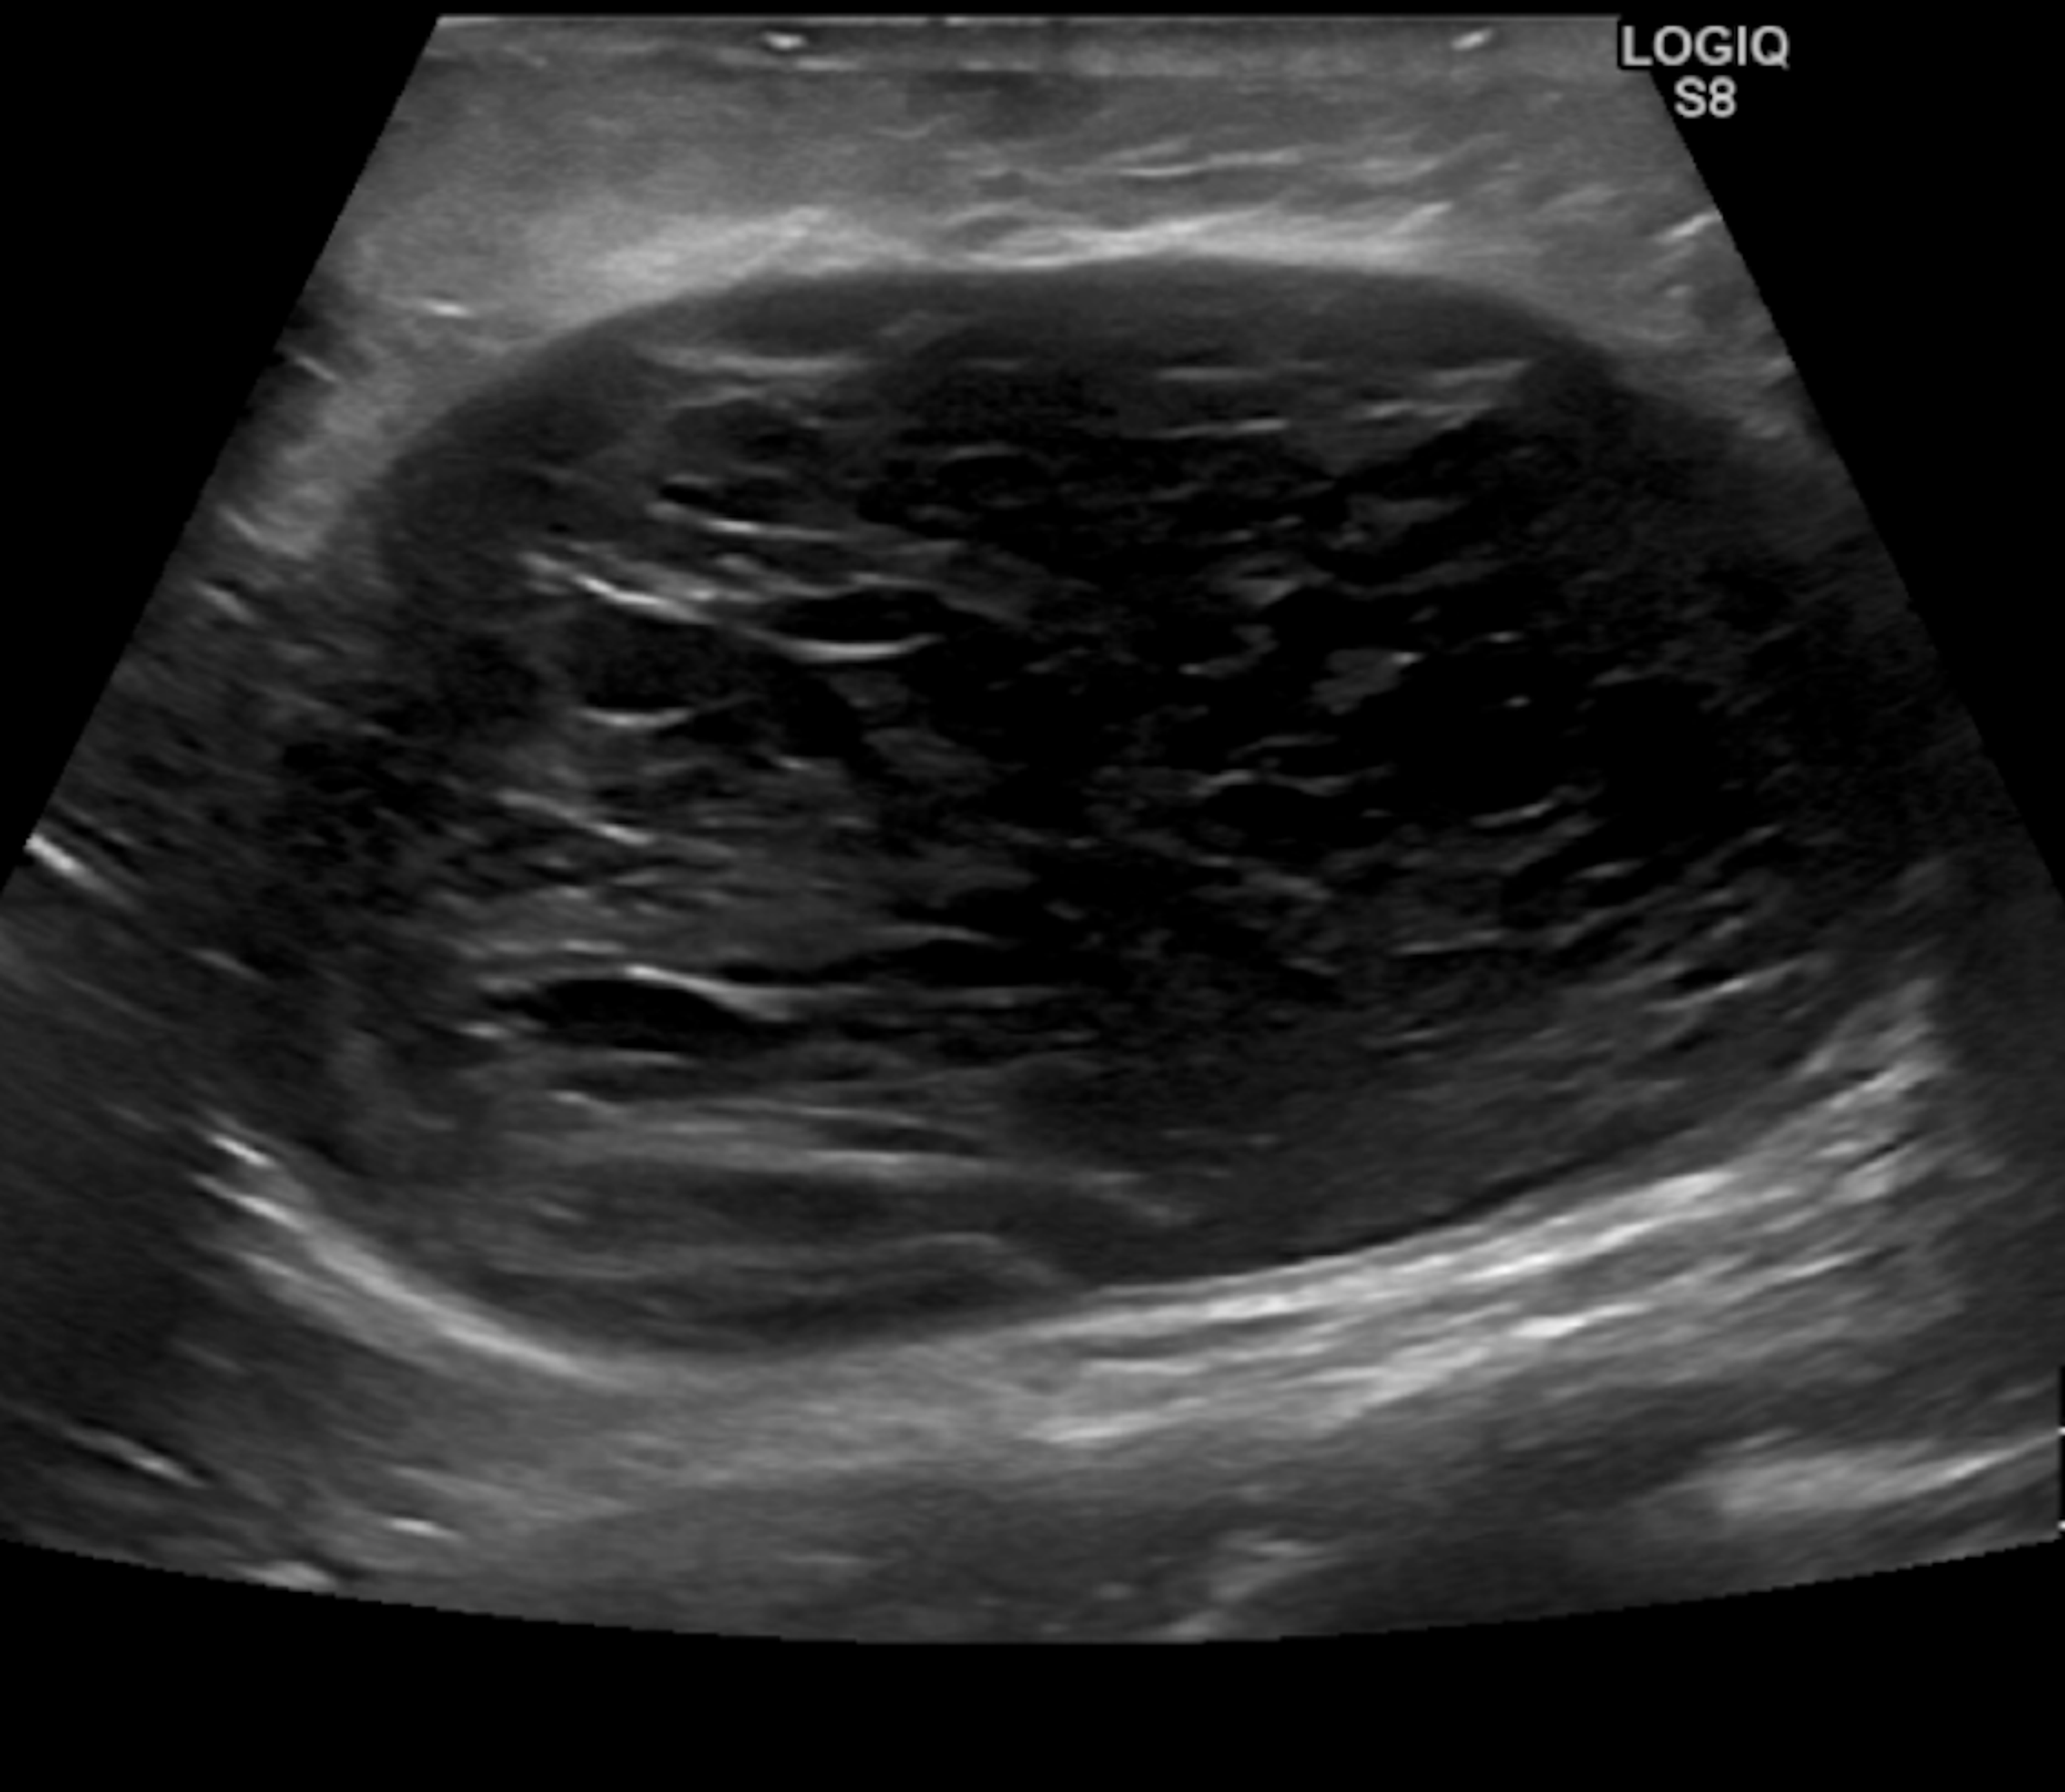

From www.semanticscholar.org

Ultrasoundguided drainage of a seroma following tumescent liposuction Can You Put Heat On A Seroma It most often occurs after surgery, but it can also happen due to injury. Applying a warm compress or heating pad to a seroma can help. This article examines seroma treatment to. warm compresses help seromas to heal. — 5 natural ways to help get rid of a seroma 1. Not only will it improve drainage and reabsorption,. Can You Put Heat On A Seroma.